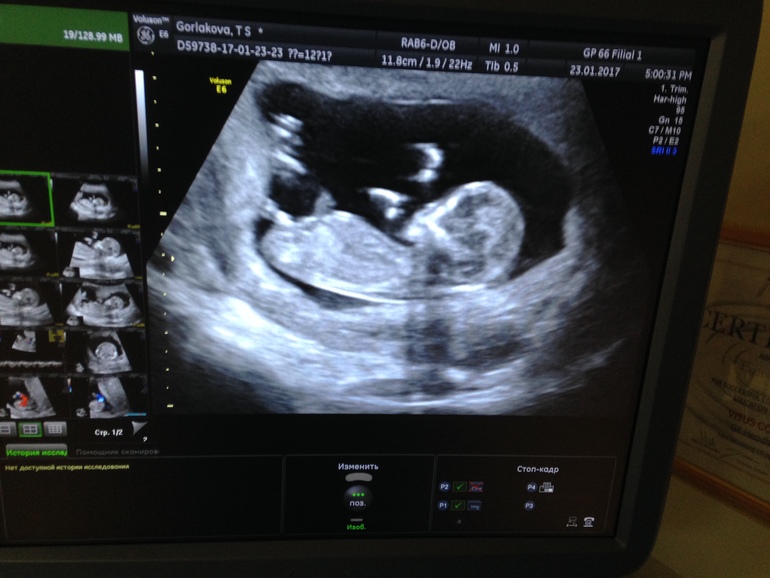

УЗИ, КТГ, доплердевочки добрый вечер! посмотрите пожалуйста и у нас кто, врач даже не предположила

Вы очень далеко фоткаете а приблизить нельзя... вообще не видно ничего... вы бы причинное место выложили)

Мне врач показала как она определяет-по половому углу .Те если между лоюком и писюлькой (сейчас больше на минипенис похож) примерно 90 и меньше градусов -значит девочка. Если около 180- мальчик.

У вас на мальчика похож.

У моей на узи прям совсем близко к лобку был этот минипенис.Прям лежал.

А у вас далеко.

По одной фотке не понять. Мне пол сказали в 11 недель и пять дней. Также сделали 3D фото и видео узи. На оборудовании последнего поколения пол рано увидеть можно.

вот мальчик истинный)) у вас вроде нет такого торчка

только вот так могу) посмотрите пожалуйста)